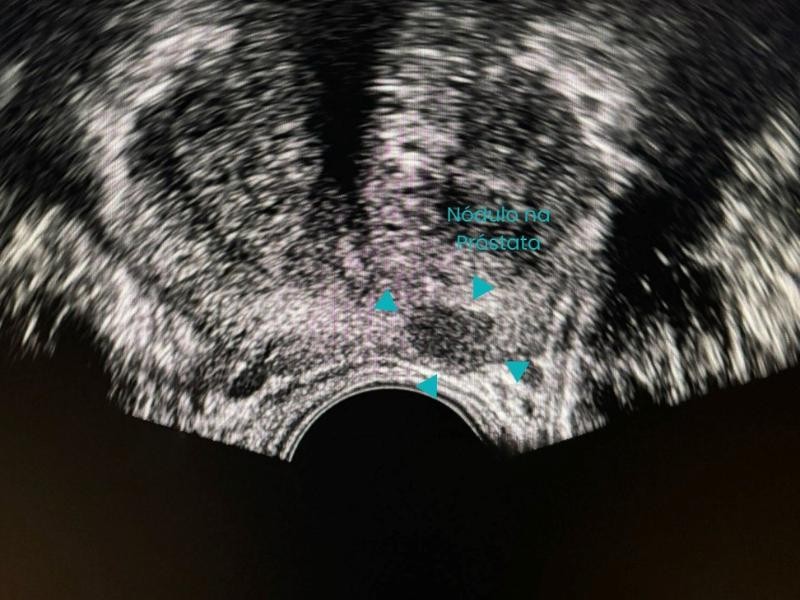

A Biópsia Guiada por Imagem é um procedimento minimamente invasivo que utiliza tecnologias como ultrassom, tomografia computadorizada ou ressonância magnética para orientar a introdução de uma agulha de biópsia até o local exato da lesão. Essa precisão é o que permite a coleta segura de amostras para análise laboratorial. A Biópsia Guiada por Imagem é realizada com equipamentos de última geração, garantindo conforto e segurança do paciente. Além disso, a técnica reduz a necessidade de cirurgias abertas e acelera o diagnóstico, sendo essencial para identificar tumores, infecções e doenças inflamatórias.

Durante a Biópsia Guiada por Imagem, o paciente é posicionado de forma estratégica, e o médico radiologista intervencionista utiliza imagens em tempo real para direcionar a agulha até o ponto exato do tecido ou amostra a ser coletado.

A Biópsia Guiada por Imagem é essencial para diagnosticar cânceres de mama, fígado, pulmão, rim, tireoide, além de lesões musculoesqueléticas e linfonodais.

Lesões suspeitas em exames de imagem ou exames físicos, como nódulos, massas ou áreas de captação anômala, são as principais indicações. Nos casos de tumores, quanto mais precoce a realização da Biópsia Guiada por Imagem, maiores as chances de detecção em estágios iniciais com melhor prognóstico para o paciente.